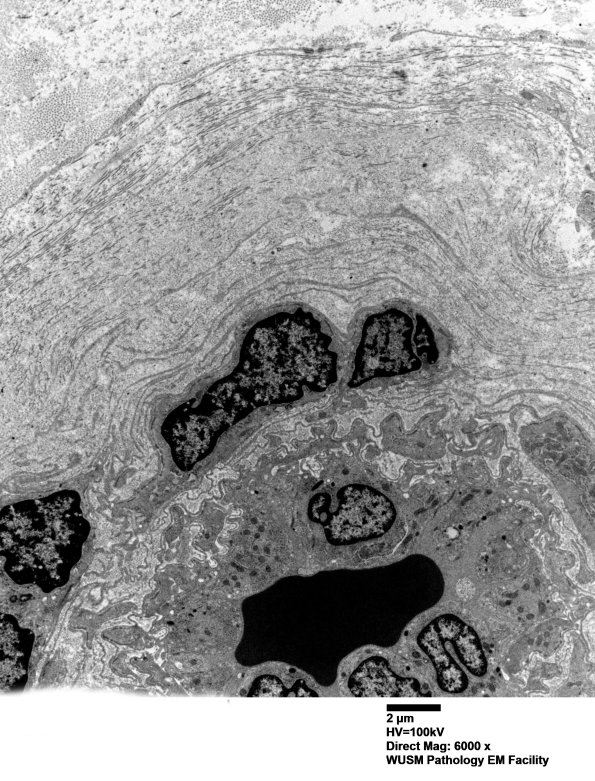

Washington University Experience | VASCULAR | Hypoxia-Ischemia, fetal-neonatal | White Matter | 6C5 (Case 6) EM 014 - Copy

6C5 (Case 6) EM 014 - Copy